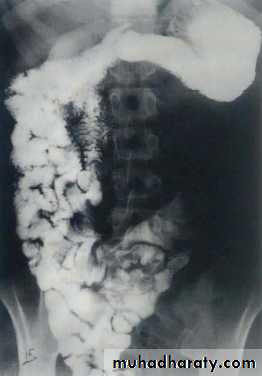

Small bowel obstruction

Large bowel obstruction

Valvulae conniventes

Present

Absent

Number of loops

Many

Few

Distribution of loops

Central

Peripheral

Haustra

Diameter

3 – 5 cm

More than 5 cm

Radius of curvature

Small

Large

Fecal material

Causes of bowel dilatation

• Mechanical SB obstruction : small bowel dilation with normal or reduced caliber of colon• Mechanical LB obstruction: dilated colon down to the point of obstruction. May be accompanied by small bowel dilation if the ileocecal valve becomes incompetent